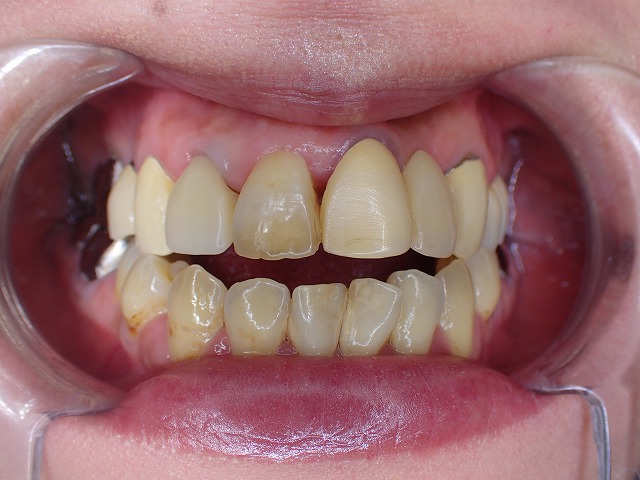

一応の根管治療をしてファイバーコアを制作

根管治療後ファイバーコアを製作

自由診療はお勧めできないので、健康保険のCAD/CAM冠を制作

自由診療は状態のよくない歯には

おすすめしていません。